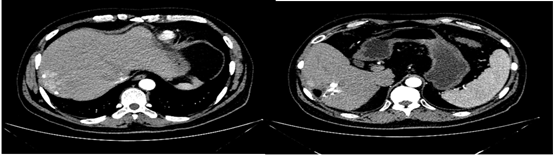

2018-12-11腹部CT检查提示,肝硬化、脾略大、门静脉高压;肝S6占位性病变,考虑原发性肝癌;肝S7段2枚结节;肝多发小囊肿,肝右叶钙化灶;双肾囊肿。

图片

图:腹部CT检查(2018-12-11)